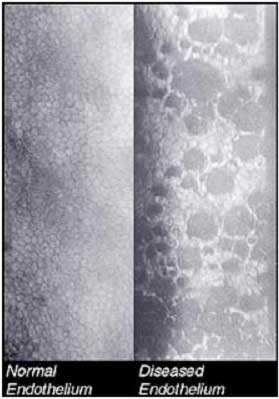

Your eye surgeon will be the best judge to decide whether you can undergo microincision phaco-surgery. Each patient undergoing cataract surgery at our centre is examined in detail to assess the endothelial count of the cornea using the automated Specular Microscope. This facility at Shroff Eye Centre is one of the very few available in the Capital. Based on findings of the endothelial count by specular microscopy it may be necessary to alter certain medication used at the time of surgery. If the endothelial cell count is low we are using BSS Plus and Viscoat, which are imported medicines, to minimize loss of the already depleted endothelial cell counts during surgery.